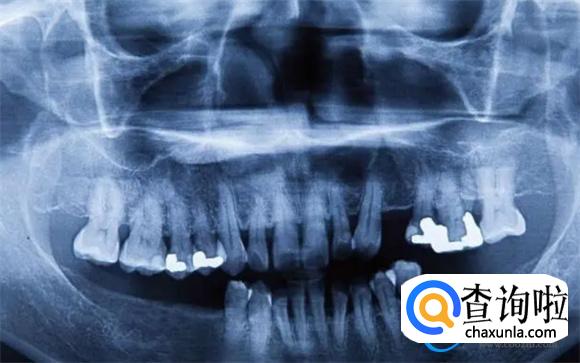

其实部分人群出现了牙龈萎缩、牙齿松动的时候,应该及时的去医院做牙齿x光线的检查,牙齿可以保留的情况下,就通过正畸内固定的方式来进行治疗。一般通过这样的治疗方式能够有效的改善牙齿松动的症状,并且能够尽快的恢复牙齿的咀嚼能力,避免出现牙齿脱落的情况。